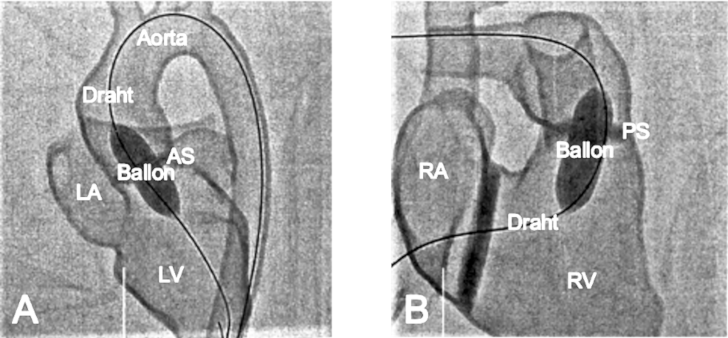

Die erste Übung erfolgte an einem 3D-gedruckten Herzmodell des linken Herzens mit physiologischer Herzanatomie. Dazu wurde es in anterior-posteriorer (siehe Abbildung 4 [Abb. 4], Punkt A) und lateraler (siehe Abbildung 4 [Abb. 4], Punkt B) Ebene durchleuchtet. Ziel dabei war die retrograde Sondierung des linken Herzens über die absteigende Aorta. Analog wurde eine Übung an einem Modell mit physiologischer Anatomie des rechten Herzes durchgeführt. Den TN wurde anhand dieser Übung auch die intrakardiale Messung von Druckkurven, Sättigung und des Flows nähergebracht. Dabei wurde besonders auf sogenannte „wire-skills“, wie die Technik des Katheterwechsels und die Steuerung des Führungsdrahtes sowie des Katheters eingegangen.

Abbildung 4: Einfluss der Projektionsebenen auf die anatomische Darstellung während der Durchleuchtung eines 3D-gedruckten Herzmodells mit physiologischer Herzanatomie des linken Herzens in zwei Ebenen. (Aorta = Aortenbogen, LV= linker Ventrikel, LA= linker Vorhof) A) Darstellung des 3D-gedruckten Herzmodells in anterior-posteriorer Durchleuchtung. B) Darstellung des 3D-gedruckten Herzmodells in lateraler Durchleuchtung.

Anschließend wurden den TN die Schritte für die interventionelle Therapie der häufigsten AHF demonstriert. Dabei wurde besonders auf die Funktionsweise eines Ballonkatheters und des zugehörigen Indeflators eingegangen, sowie die In- und Deflation geübt (siehe Abbildung 5 [Abb. 5]). Für den Verschluss des ASD werden Schirmchen (Okkluder) verwendet. Bei einem PDA können Schirmchen oder Metallspiralen (Coils) eingesetzt werden. Beide Verschlussimplantate besitzen eine spezielle Technik zum richtigen Positionieren und Lösen des Führungskatheters. Anschließend an die Demonstration konnten die TN die Interventionsschritte und die Positionierung der Implantate an den Modellen üben.

Abbildung 5: Fluoroskopische Dokumentation der Ballondilatation von Stenosen im 3D-gedruckten Herzmodell A) Ballondilatation einer valvulären Aortenstenose. Der inflatierte Dilatationsballon ist im Bereich der Aortenklappe positioniert, der lange Führungsdraht kommt aus der deszendierenden Aorta und liegt mit der Spitze im linken Ventrikel. B) Ballondilatation einer valvulären Pulmonalstenose. Der inflatierte Dilatationsballon ist im Bereich der Pulmonalklappe positioniert, der lange Führungsdraht kommt aus der Vena cava inferior über den rechten Vorhof in den rechten Ventrikel und liegt mit seinem Ende in der rechten Pulmonalarterie (Aorta = Aortenbogen, AS= Aortenstenose, PS= Pulmonalstenose, LV= linker Ventrikel, LA= linker Vorhof, RV= rechter Ventrikel, RA= rechter Vorhof)